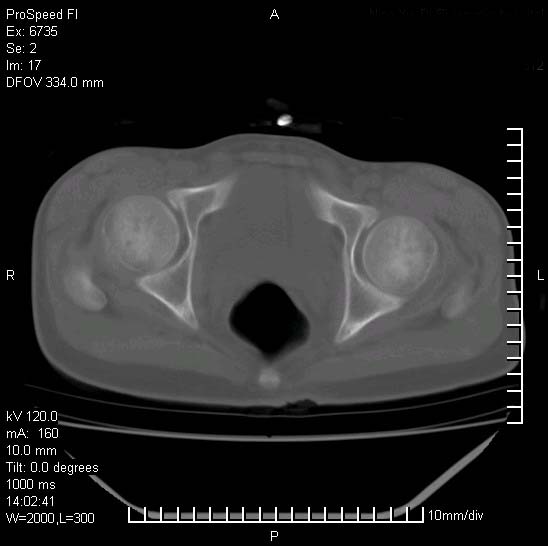

患者自诉胯部疼痛两年余,在当地服用中药,半月前至本院考虑骶髂关节结核,给予抗痨治疗。现发展至右下肢疼痛明显,活动受限,以膝关节处明显,拍膝关节平片无明显异常。

两侧骶骼关节改变,考虑强直性脊炎

左侧骶髂关节面限局性骨破坏,边缘硬化关节腔见钙化物;不出外tb

考虑强直性脊炎,建议查hla-b27

右侧骶髂关节也有类似改变,只是较左侧轻,首先考虑强直性脊柱炎,不除外结核,建议作hla-b27检查。

典型强脊炎改变,髋关节亦有累及

符合强直性脊柱炎表现。